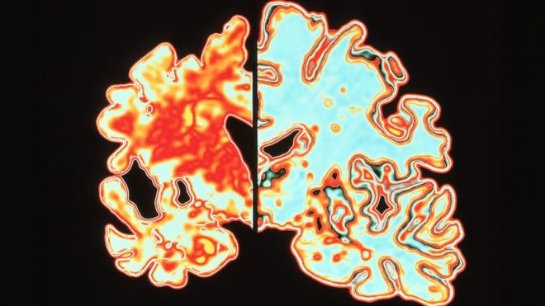

Ученые работали над остановкой нарастания повреждающих белков, таких как амилоид и тау.

Эти генетические ошибки включали накопление амилоида, которое приводит к повреждению нервных клеток у пациентов с болезнью Альцгеймера.

Эта идея, известная как гипотеза амилоидного каскада, уже почти 30 лет занимает центральное место в исследованиях заболевания.

В то же время исследование профессора Гёдерта в Кембриджском университете показало важность другого разрушающего белка – тау.